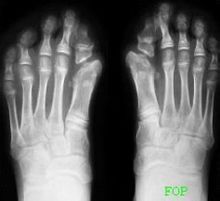

進行性肌肉骨化症患者艾西禮·科佩耶爾進行性肌肉骨化症(myositisossificansprogressiva, MOP)又稱進行性骨化性纖維發育不良(fibrodys-plasiaossificansprogressiva,FOP)是一種罕見的遺傳性、進行性結締組織疾病,以多關節進行性活動障礙和進行性橫紋肌異位骨化為特徵。雖然這是種顯性遺傳疾病,但大半的病患仍為突變、自然產生,不一定追溯得到家族史。根據文獻記載此疾最早的病例可追溯至十六世紀末,至今全球病例數不超過千人,患上這種疾病的幾率是兩百萬分之一。

進行性肌肉骨化症 進行性肌肉骨化症常常會從患者的身體中央部分,也就是頸部、背部,一直到骨盆,四肢比較大的關節開始出現僵硬,慢慢的這些地方就出現鈣化。

進行性肌肉骨化症主要的致病原因是第四對染色體長臂上的基因(ACVR1)產生突變,影響骨骼的形成與修復,產生大量錯誤的蛋白質。其患者最大的特色為骨骼先天的異常及進行性的肌肉骨化 。